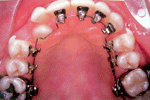

มาถึง การจัดฟันด้านใน

การจัดฟันแบบใสและขั้นตอนการจัดฟันมีรูปคนน่ารักจัดฟันด้วย    การจัดฟันแบบใสและขั้นตอนการจัดฟันมีรูปคนน่ารักจัดฟันด้วย       การจัดฟันแบบใสและขั้นตอนการจัดฟันมีรูปคนน่ารักจัดฟันด้วย

การจัดฟันแบบใสและขั้นตอนการจัดฟันมีรูปคนน่ารักจัดฟันด้วย   >>  การจัดฟันแบบใสและขั้นตอนการจัดฟันมีรูปคนน่ารักจัดฟันด้วย  >> การจัดฟันแบบใสและขั้นตอนการจัดฟันมีรูปคนน่ารักจัดฟันด้วย

>>   การจัดฟันแบบใสและขั้นตอนการจัดฟันมีรูปคนน่ารักจัดฟันด้วย     >>>>>>>  การจัดฟันแบบใสและขั้นตอนการจัดฟันมีรูปคนน่ารักจัดฟันด้วย

และการจัดฟันแบบสีเหมือนฟัน